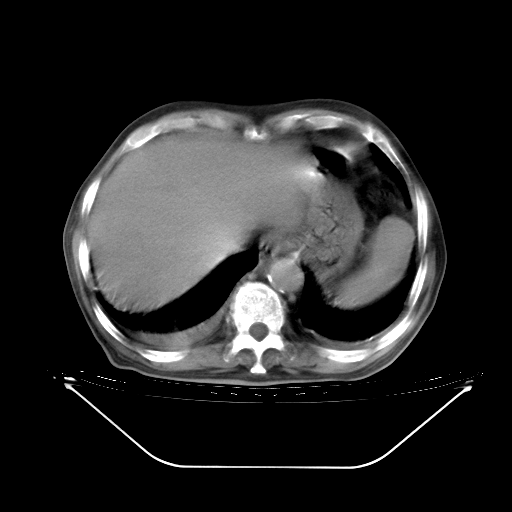

今天复查肺部CT,发现双肺广泛磨玻璃样改变。所以我把3月19日和5月9日相隔50天的肺部CT上传。请大家会诊。

2009年3月19日肺部CT片。

2009年3月19日肺部CT